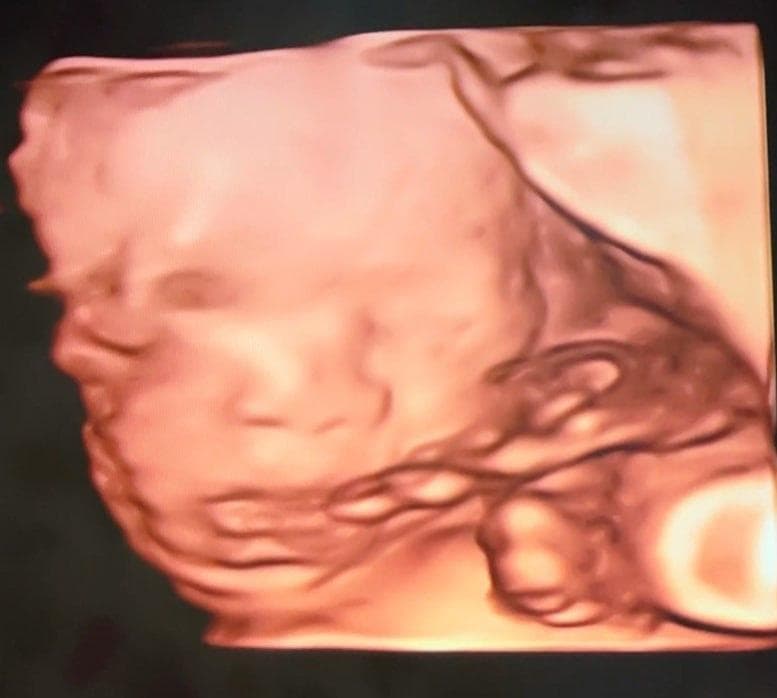

3장 모두 같은 날 촬영한 24주차 딸의 입체 초음파 사진입니다.

위 태아 사진을 보면 눈사이거리가 좀 멀어보입니다.

(다른 태아들 사진을 검색해보면 대부분 더 좁아보이더군요.)

그리고 다른 의사선생님이 보시기에 태아의 코 크기나 콧볼 크기는

다른 태아들과 비교해서 평균인지, 아니면 크거나 작은지 궁금합니다.